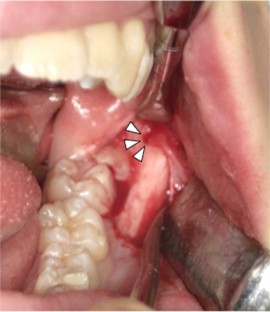

Fig. 5